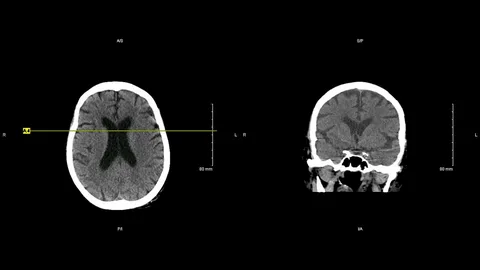

The non-contrast CT imaging market has been growing steadily over the years, driven by factors such as an aging population, increasing prevalence of chronic diseases, advancements in CT technology, and rising awareness about the benefits of non-contrast imaging. The market has also witnessed significant technological developments, including the introduction of low-dose CT techniques, iterative reconstruction algorithms, and multi-detector CT scanners, which have improved image quality and reduced radiation exposure. Additionally, the growing demand for early and accurate diagnosis, coupled with the expanding applications of CT imaging in various medical specialties, has contributed to the market’s growth. Non-contrast CT imaging is utilized in fields such as neurology, cardiology, oncology, and orthopedics, among others.

Neurology